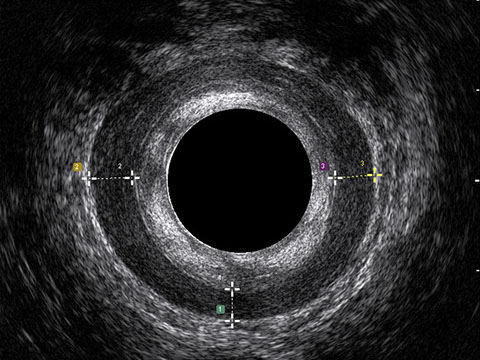

L’ecografia transanale permette di distinguere la sottomucosa che riveste il canale anale, lo sfintere anale interno, e lo sfintere anale esterno.

Le principali indicazioni all’esecuzione di tale esame sono lo studio dell’integrità delle strutture muscolari nei casi di incontinenza fecale, lo studio topografico dei processi settici perianali (ascessi e fistole) e lo studio dei processi proliferativi epiteliali (carcinoma anale).